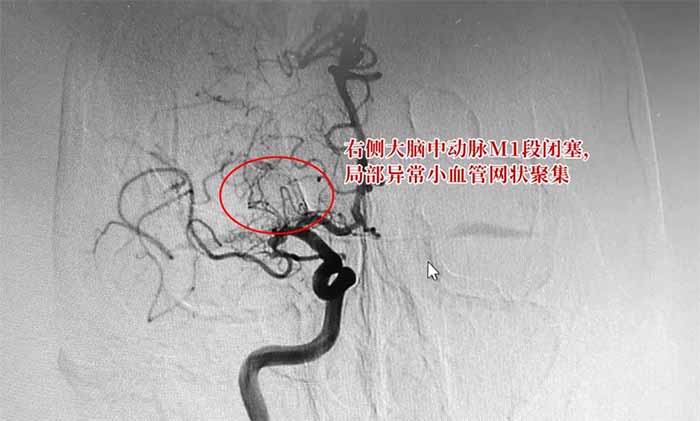

烟雾病是一种慢性闭塞性脑血管疾病,以双侧颈内动脉末端和(或)大脑前动脉、大脑中动脉起始部缓慢进展性狭窄以致闭塞,出现代偿性异常血管网为特点,因其异常血管网在脑血管造影时似“烟雾缭绕”,故称为“烟雾病”。

▲ 烟雾病DSA检查影像